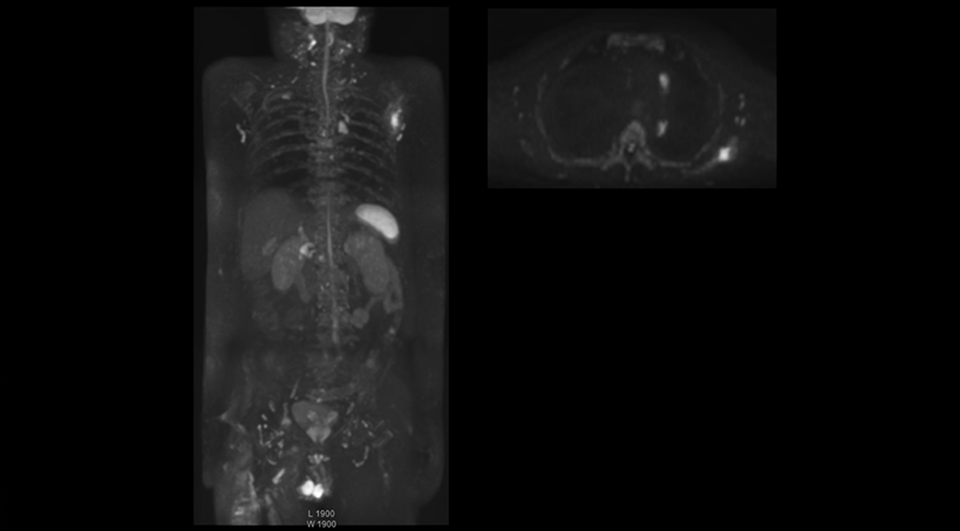

Radiologist Hiroshi Nobusawa, MD, PhD, explains that the coronal DWIBS protocol for whole body DWI is excellent for visualizing lesions in oncology patients. “About 90% of the DWIBS exams are done in this type of patients. The remainder of DWIBS exams are performed to gain information in cases of fevers of unknown origin,” he says. in image acquisition and postprocessing algorithms.”“mDIXON TSE sequences allow simultaneous characterization of morphological changes from the in-phase T2-weighted images and visualization of edematous changes, thanks to the water T2-weighted images from the same acquisition. Anatomical and morphological considerations could be a partial or complete ligament tear, a bony avulsion or hematoma.” “For soft tissue assessment mDIXON brings similar benefits. For example in one T2-weighted mDIXON TSE acquisition, having the multiple contrasts helps us assess abnormalities in peripheral nerves fascicles, which may be due to anatomical or inflammatory changes..” “In peripheral joints, we get good image quality in difficult areas with mDIXON TSE. Fat suppressed images appear homogeneous over the entire image, even with large coverage at 3.0T – for instance in scapular or hip girdles – or in the bearing areas or around metal prostheses*, where fat suppression is often deficient with STIR or spectral fat suppression, causing diagnostic difficulties. If a diagnostic image is right the first time, we don’t need to repeat or add a sequence.” “mDIXON TSE sequences allow simultaneous characterization of morphological changes from the in-phase T2-weighted images and visualization of edematous changes, thanks to the water T2-weighted images from the same acquisition. Anatomical and morphological considerations could be a partial or complete ligament tear, a bony avulsion or hematoma.” “For soft tissue assessment mDIXON brings similar benefits. For example in one T2-weighted mDIXON TSE acquisition, having the multiple contrasts helps us assess abnormalities in peripheral nerves fascicles, which may be due to anatomical or inflammatory changes..”

“The DWIBS sequence’s value in oncology cases is due to the high contrast it creates between lesions and surrounding tissue. Whole body DWI is requested by physicians who need to clarify TNM staging or determine therapeutic strategies, oncologists in need of diagnosis or follow-up scans, surgeons who need to see the presence of distant lesions that are sometimes difficult to detect by CT before surgery, and urologists for the evaluation of bone lesions, and the effect of chemotherapy and radiotherapy.”

After implementing the improved whole body protocol, the radiology team initially did not see a large increase in referrals, although Dr. Nobusawa saw clinical cases where the DWIBS images provided him valuable information for diagnosis. This is why Dr. Nobusawa and Mr. Naka started to actively educate referring physicians about the value of whole body DWIBS. They organized several presentations for physicians in the hospital, where they explained how DWIBS can be of value in oncology patients. The information it provides can be useful for physicians when staging cancer, as well as when determining or adjusting treatment strategy. Mr. Naka remembers some cases where DWIBS provided remarkable information. “In one example, DWIBS visualized bone lesions that could not be seen on PET or SPECT. In another case we had found a bone lesion when a normal L-spine scan for narrowing of the disk space was done. One extra DWIBS scan (2 stations, 8 minutes) demonstrated a lesion that later was confirmed to be the primary region of cancer.”